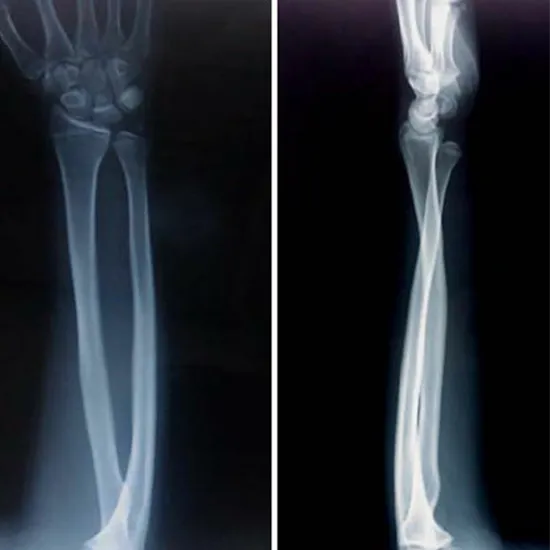

X-ray Left Arm AP & LAT

Arm X-rays are a safe and painless means of seeing the arm with a little radiation dose. The arm consists of the shoulder joint, the upper arm bone (humerus), the elbow, the forearm bones (radius and ulna), the wrist, and the surrounding soft tissues (skin and muscles).

It is advised in the case of arm symptoms such as discomfort, tenderness, or swelling. This technique detects fractures, infection, irregular growth, and dislocations in the arm's joints. It can also be used as a surgical guide and monitor the healing process following surgery.